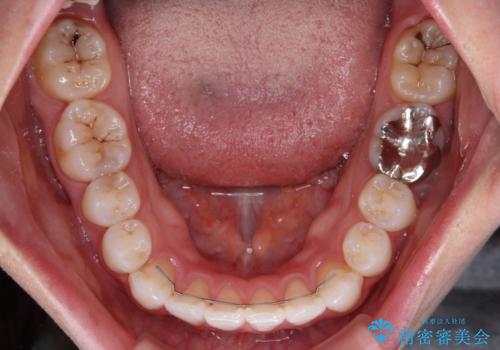

補助装置を使用したことで、口元が突出することもなく、スムーズに仕上げることができました。